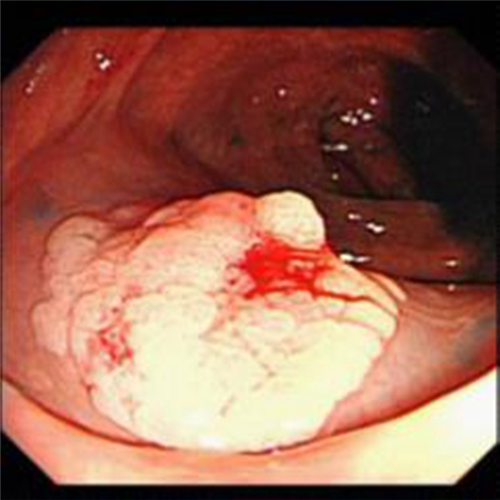

直腸息肉圖片

直腸息肉糜爛的